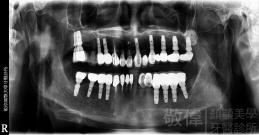

治療前X光   治療後X光

治療前-全口X光   治療後-全口X光